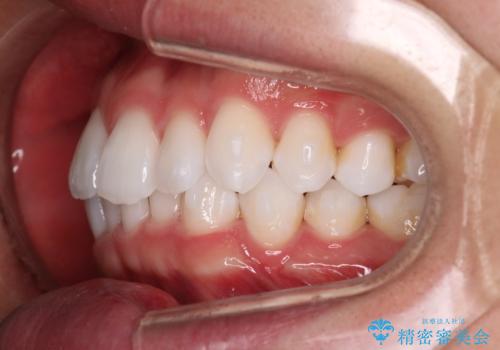

治療症例の内容

- 患者様

- 20代男性

- 矯正装置

- インビザライン

- 治療期間

- 1年

- 治療回数

- 5-10回

- 治療計画

- がたつきが気になるとの事で来院されました。

目立たない装置で費用も抑えたいとの希望があったため、インビザラインにて治療をすることとなりました。

上下顎ともにIPR(歯と歯の間を削る処置)を行い歯並びを整える治療計画を立てました。

治療当初は、計画通りに治療が進むか心配でしたが、しっかりマウスピースを使用していただいたことで

治療期間も長引くことなく歯並びを綺麗に改善することが出来ました。

患者様の希望もあり、前歯の微調整で1回リファイメント(マウスピースの再発注)を行いました。

患者様の希望に沿う治療を提案することができ良かったと思います。